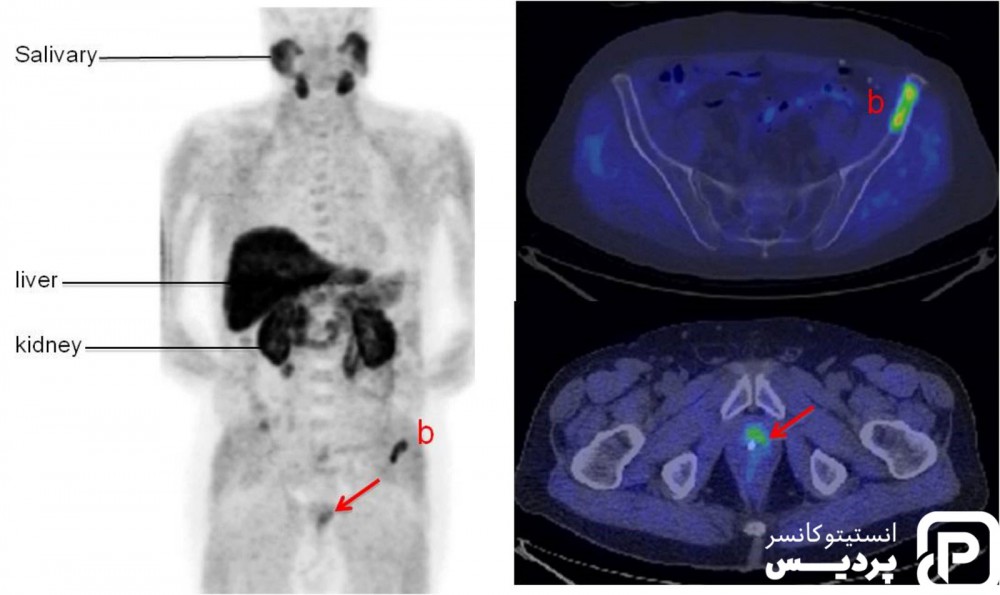

اسکن استخوان در تشخیص سرطان پروستات

اگر سرطان پروستات در قسمت های دور بدن گسترش یابد، اغلب ابتدا به استخوان ها می رود. اسکن استخوان می تواند نشان دهد که سرطان به استخوان رسیده است یا خیر. برای انجام این اسکن، مقدار کمی از مواد رادیواکتیو با دوز پایین به بیمار تزریق می شود تا نواحی آسیب دیده به خوبی مشخص شوند. یک دوربین خاص رادیواکتیویته را تشخیص داده و تصویری از اسکلت منطقه مورد نظر ایجاد می کند. اسکن استخوان نشان دهنده سرطان در است که برای اطمینان از وجود سرطان در استخوان آزمایش های دیگر ضروری است.

اسکن توموگرافی کامپیوتری (CT) در تشخیص سرطان پروستات

سی تی اسکن از اشعه ایکس برای ساخت تصاویر دقیق از نقاط مختلف بدن استفاده می شود. در صورتی که وجود سرطان بر اساس نتیجه آزمایش های دیگر چون DER، سطح PSA و نمره گیلسون مشخص شده باشد، انجام CT اسکن ضروری نمی باشد. گاهی اوقات، سلول های سرطان پروستات به غدد لنفاوی مجاور رسیده و انجام اسکن توموگرافی تشخیص را آسان می نماید.